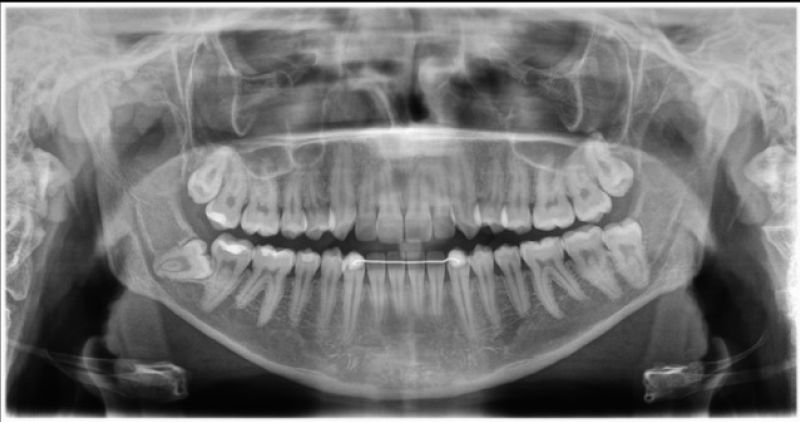

Vor der Behandlung wird durch Röntgenbilder die genaue Lage der Weisheitszähne bestimmt. Der Eingriff erfolgt unter lokaler Betäubung, auf Wunsch auch unter Kurznarkose. In vielen Fällen wird das Zahnfleisch geöffnet, und der Zahn kann in Stücken entfernt werden, um das umliegende Gewebe zu schonen. Der Eingriff dauert in der Regel zwischen 20 und 60 Minuten.